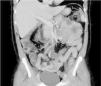

Varón de 49 años con extirpación de melanoma nodular estadio IIA en el brazo izquierdo hace 2 años. Acude por dolor abdominal epigástrico de 2 semanas de evolución, fiebre nocturna y síndrome constitucional. Analíticamente destaca anemia microcítica: hemoglobina 8.9g/dl, volumen corpuscular medio 73.7fl; elevación de proteína C reactiva: 220mg/l. La tomografía computarizada (TC) abdominal describe dilatación aneurismática intestinal junto a múltiples adenopatías regionales mesentéricas (figs. 1 y 2). Ante los hallazgos se realiza enteroscopia con doble balón donde se aprecia masa ulcerada, friable y dura a la toma de biopsias en primera porción yeyunal (fig. 3). En el diagnóstico diferencial también incluimos el linfoma primario intestinal, el tumor estromal gastrointestinal (GIST), el leiomiosarcoma y el adenocarcinoma. El estudio histopatológico concluye como metástasis intestinal de melanoma (figs. 4 y 5). Se realiza resección intestinal del segmento afecto y posterior inmunoterapia con nivolumab. La mayoría de los melanomas intestinales son metástasis de un melanoma cutáneo primario, con mejor pronóstico. En este caso, los antecedentes, los hallazgos endoscópicos y el análisis histopatológico aclararon el diagnóstico definitivo.